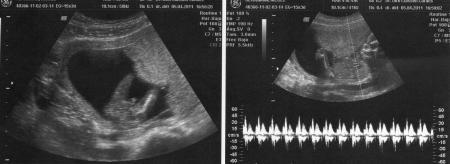

Hallo ihr Lieben, bin auch zurück von der VU und alles ist in bester Ordnung . Baby ist ca. 20 cm gross und 130 gr schwer/leicht . Herzchen hat kräftig geschlagen und wir durften einen ausgiebigen Blick zwischen die Beinchen werfen uuund was sahen wir? Einen kleinen Pippimann !!! Mein FA ist sich zu 100 % sicher und hat es sogar schon in meinen Mutterpass eingetragen. Mein Freund und mein Söhnchen waren auch dabei und haben sich na klar riesig gefreut über den männlichen Zuwachs in der Runde Hänge noch 2 Bildchen an ;-) LG Nici

Bild zu Auch zurück von der VU mit Outing und süssen Fotos ;-) - Forum für September - Mamis

... mit eindeutigen Einblicken (1. Foto) LG Nici

Auf dem linken Bild ist es ja wirklich eindeutig :o).Toll, dass dein Bauchbewohner so zeigefreudig war. Herzlichen Glückwunsch zum Sohnemann! Liebe Grüße Eolair

na das ja mal ein beweisfoto...-herzlichen glückwunsch zum sohnemann! und euer knirpsi ist auch schon ganz schön groß... Lg